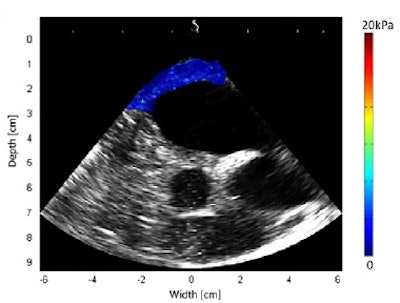

Kwiecinski and colleagues carried out an in vivo study to demonstrate that cardiac SWE can map myocardial stiffness in a beating heart. They used a standard transesophageal echocardiography (TEE) probe, comprising a 5-MHz, 64-element phased array, to perform SWE on the heart of an anaesthetized sheep in an open-chest setup.

SWE measurements recorded over a cardiac cycle showed tissue stiffness varied from 0.5 ± 0.1 to 6.0 ± 0.3 kPa in the atrium and from 1.3 ± 0.3 to 13.5 ± 9.1 kPa in the ventricles during the cycle. These values agree with previous in vivo studies on a beating heart.

Shear modulus maps of a right atrium (above) and right ventricle free wall (below) superimposed on B-mode images. The mean shear modulus within the atrial wall, acquired at atrial systole, was 1.3 ± 0.3 kPa; the mean shear modulus in the right ventricle, acquired at ventricular diastole, was 1.7 ± 0.5 kPa.Next, the researchers used the combined imaging-therapy endoscope (developed by collaborators from LabTau in Lyon) to demonstrate TEE-SWE mapping of HIFU-induced lesions in vitro. The combined transesophageal probe included a 3-MHz HIFU transducer, with a focal depth of 15-55 mm, with the standard TEE probe inserted at its center.